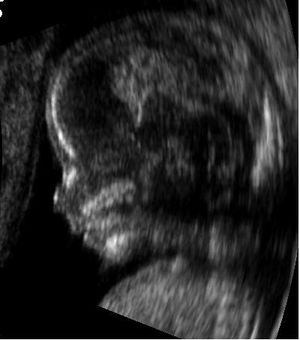

- لا يرتبط التصوير بالرنين المغناطيسي بدون وسط التباين في التصوير بالرنين المغناطيسي وكذلك التصوير بالموجات فوق الصوتية التوليدية بأي خطر على الأم أو الجنين، وهي تقنيات التصوير المفضلة للنساء الحوامل.[1]

التصوير بالرنين المغناطيسي، بدون وسط تباين في التصوير بالرنين المغناطيسي، لا يرتبط بأي خطر على الأم أو الجنين، وإلى جانب تخطيط الصدى الطبي هو الأسلوب المفضل للتصوير الطبي في الحمل.[1]